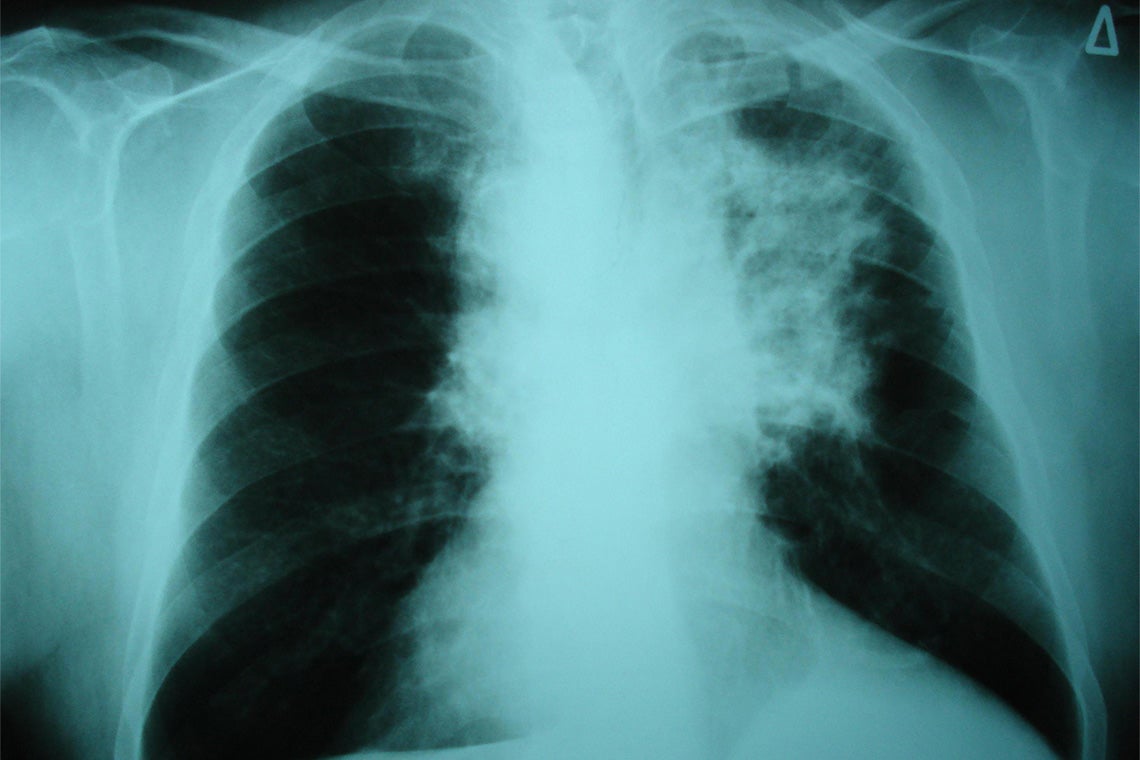

Lung cancer remains a leading cause of death from cancer in Canada and the world. Non-small cell lung cancer is the most common type of the disease, with about one fifth of cases in North America caused by EGFR mutations.